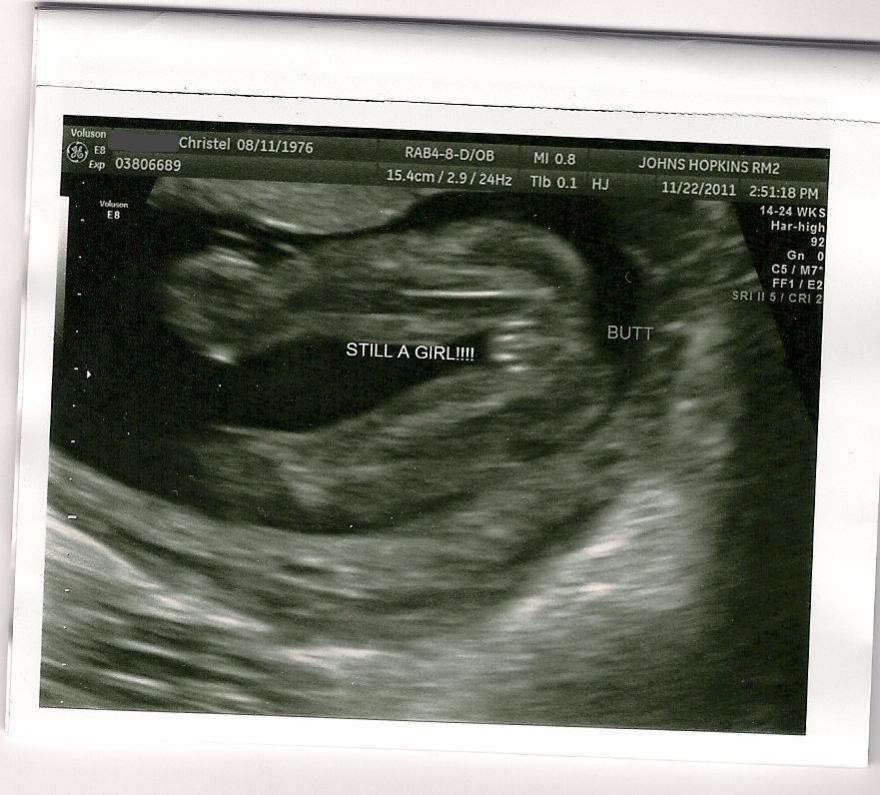

Here's mine: Attachment 1008

Yep all girl :) congrats